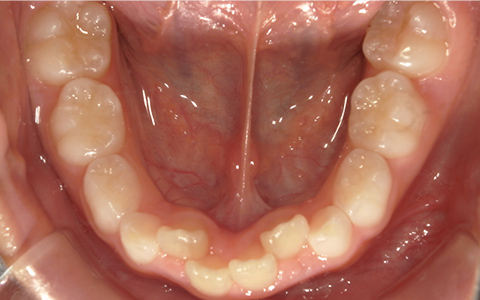

症例